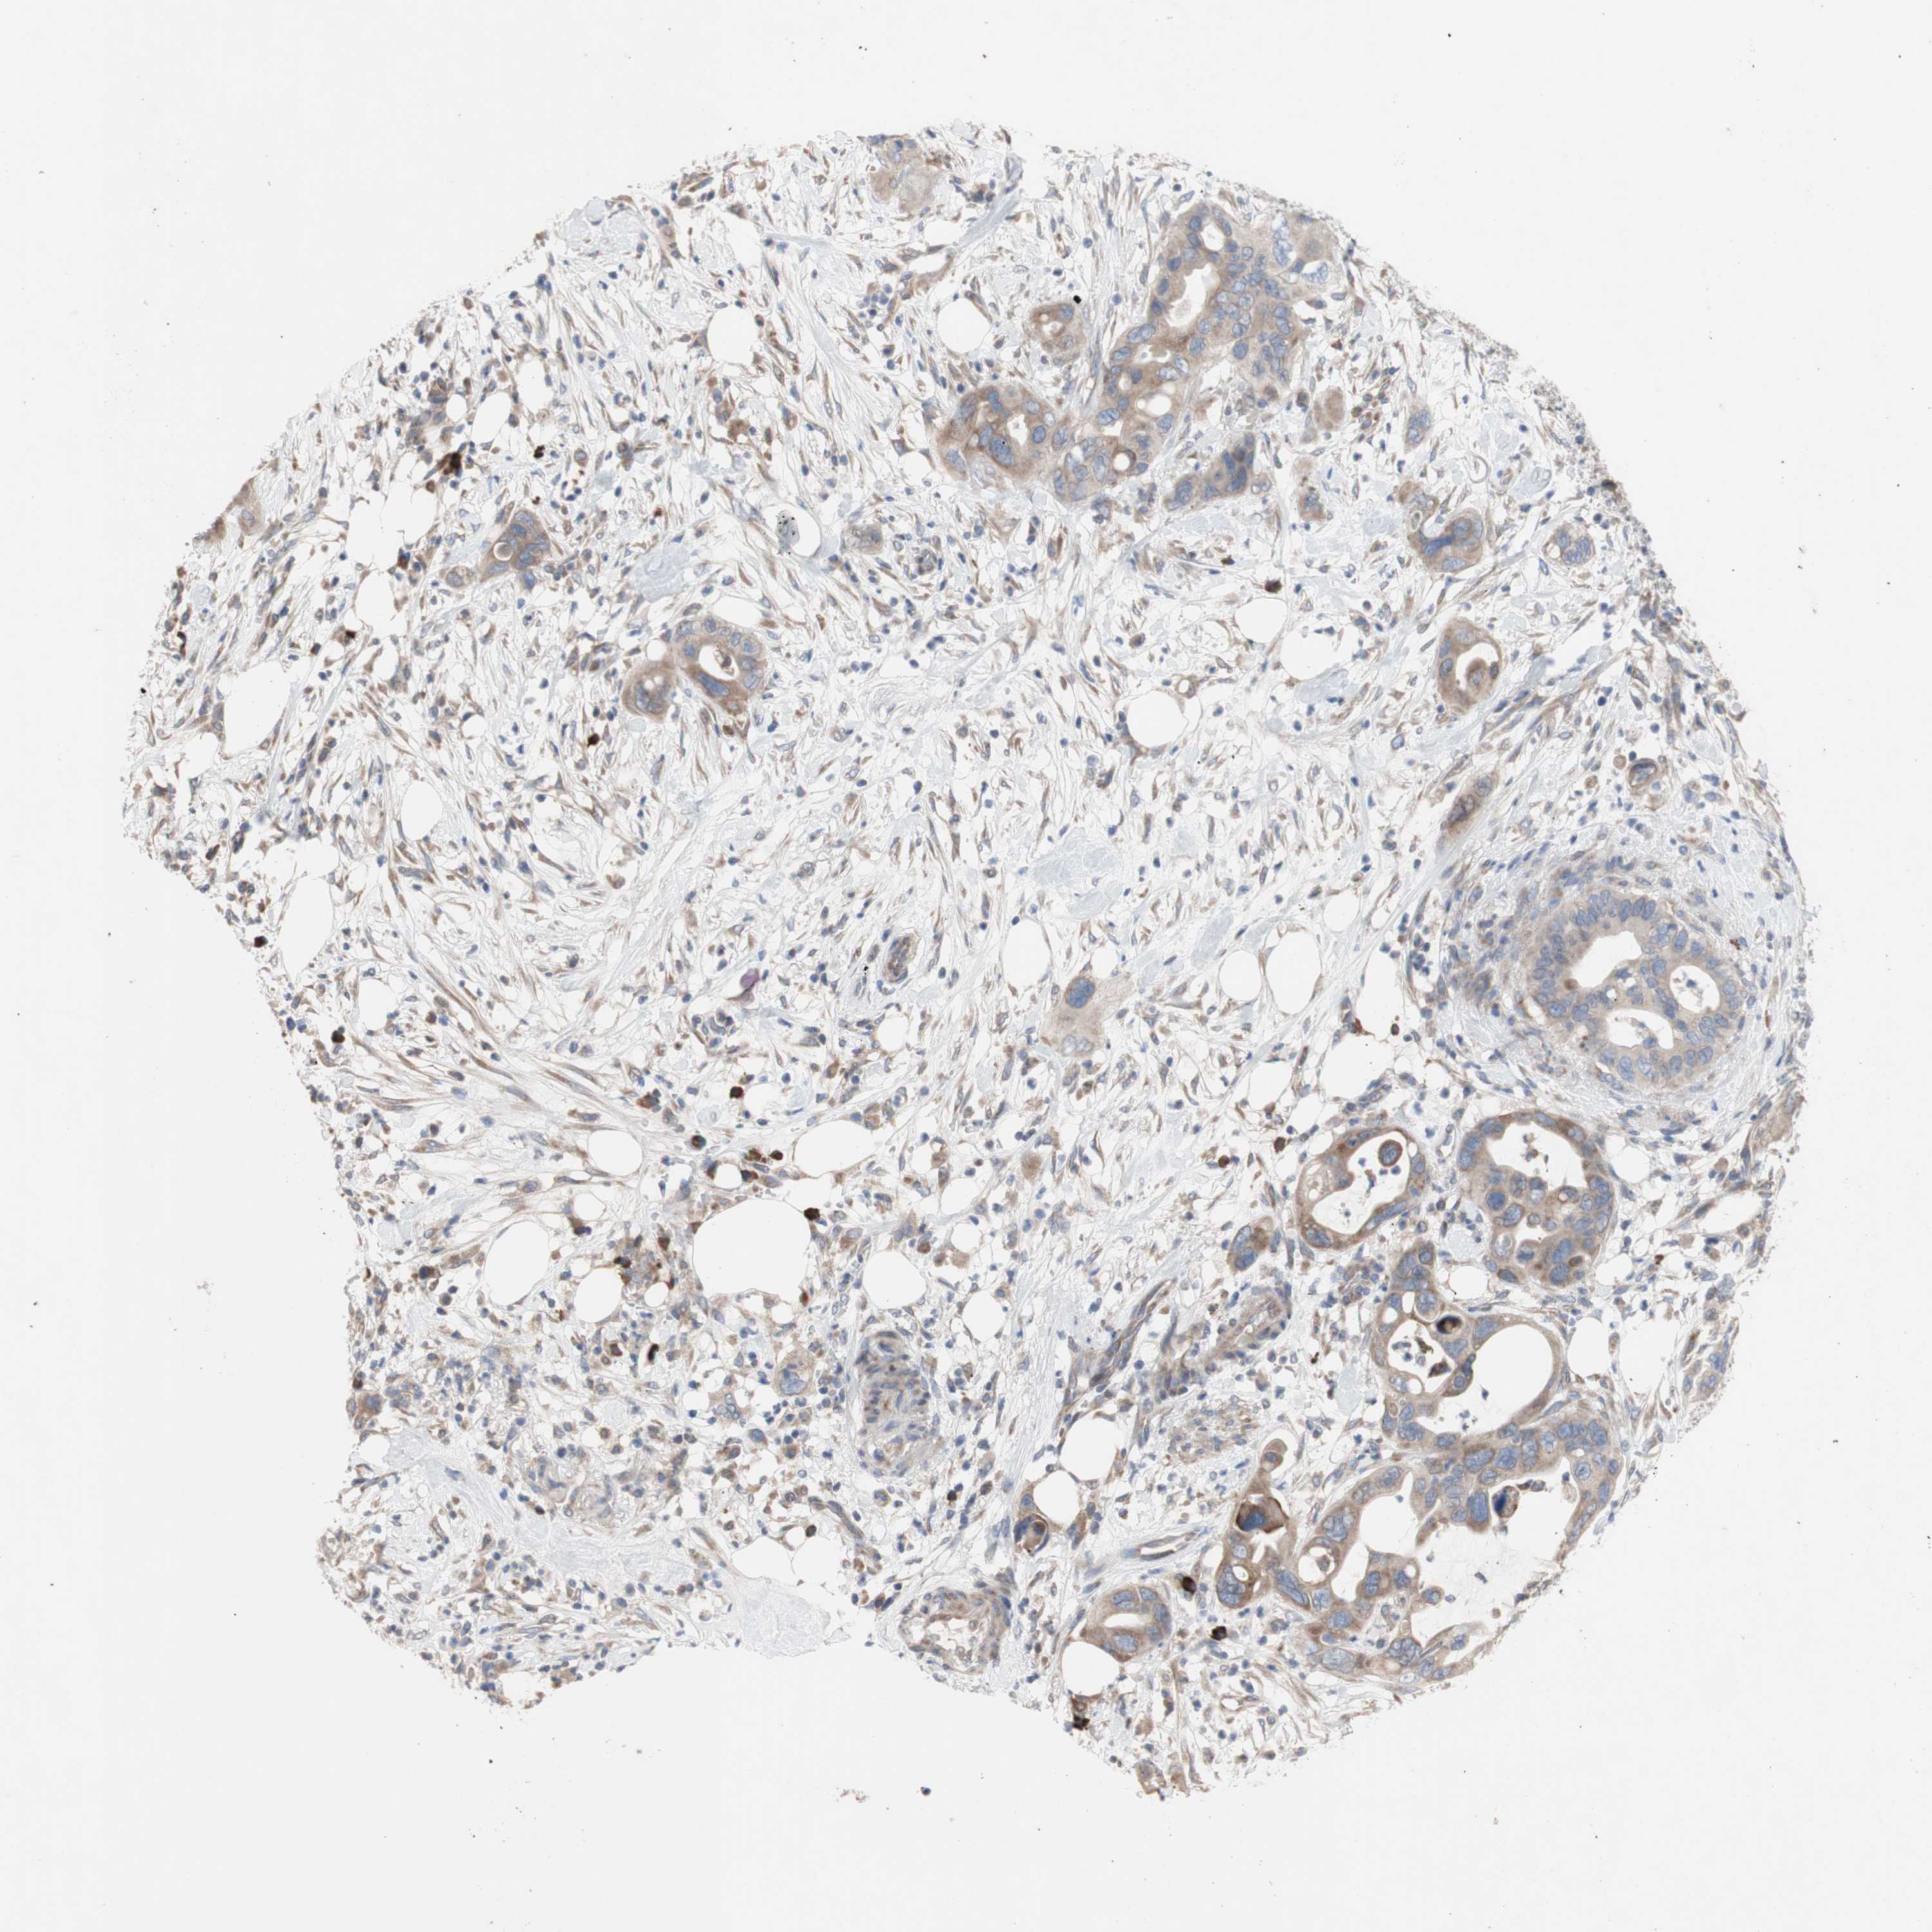

PANCREATIC CANCER - Protein expressioni

A mouse-over function shows sample information and annotation data. Click on an image to view it in a full screen mode. Samples can be filtered based on level of antibody staining by selecting one or several of the following categories: high, medium, low and not detected. The assay and annotation is described here.

Note that samples used for immunohistochemistry by the Human Protein Atlas do not correspond to samples in the TCGA dataset.

Antibody stainingi

Antibody staining in the annotated cell types in the current human tissue is reported as not detected, low, medium, or high, based on conventional immunohistochemistry profiling in selected tissues. This score is based on the combination of the staining intensity and fraction of stained cells.

Each image is clickable and will lead to virtual microscopy that enables deeper exploration of all samples and also displays staining intensity scores, fraction scores and subcellular localization as well as patient and tissue information for each sample.

Antibody HPA009295

Staining

High

Medium

Low

Not detected

Intensity

Strong

Moderate

Weak

Negative

Quantity

>75%

75%-25%

<25%

None

Location

Nuclear

Cytoplasmic/membranous

Cytoplasmic/membranous,nuclear

Adenocarcinoma, NOS